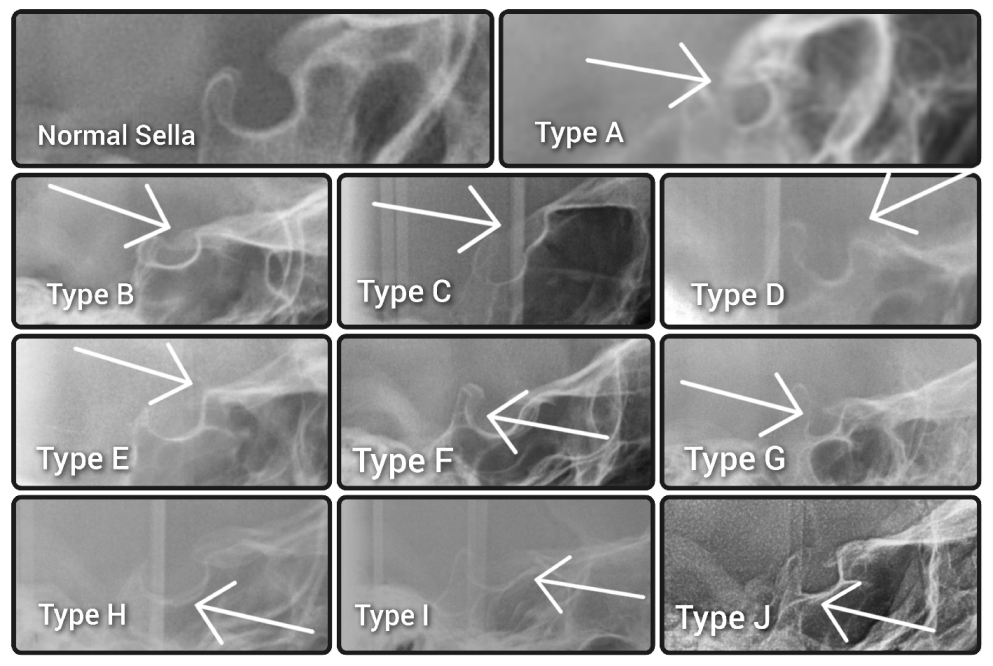

No cephalograms were made for the purpose of the study to avoid unnecessary excessive radiation. Ethical review and board approval have been waived for this study (decision reference No. KB-006/04/2022/Z). The morphologies of the sella turcicae were assessed according to the method described by Kucia et al. [15] and classified as either a normal sella turcica or ten variations, namely sella turcica bridge A—ribbon-like fusion; sella turcica bridge B—extension of the clinoid processes; C—incomplete bridge; D—hypertrophic posterior clinoid process; E—hypotrophic posterior clinoid process; F—irregularity (notching) in the posterior part of the sella turcica; G—pyramidal shape of the dorsum sellae; H—double contour of the floor; I—oblique anterior wall; or J—oblique contour of the floor, as presented in Figure 1.

Figure 1. Morphology of normal sella turcica and types of abnormalities. Normal sella turcica. Type A—sella turcica bridge type A—ribbon-like fusion. Type B—sella turcica bridge type B—extension of the clinoid processes. Type C—incomplete bridge. Type D—hypertrophic posterior clinoid process. Type E—hypotrophic posterior clinoid process. Type F—irregularity (notching) in the posterior part of the sella turcica. Type G—pyramidal shape of the dorsum sellae. Type H—double contour of the floor. Type I—oblique anterior wall. Type J—oblique contour of the floor.